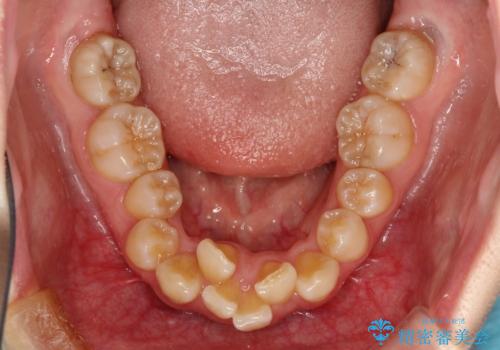

- 治療計画

- 口元の閉じにくさと、前歯のでこぼこの歯並びを気にして来院された患者様です。

口元を積極的に引っ込めるために、上下左右の小臼歯計4本を抜歯することとしました。

咬み合わせが深く、咬合力強いため、補助装置を使用しながら積極的に口元を下げることとしました。